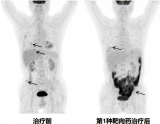

吴美其:18F-FDG PET/CT 对胰腺导管腺癌一线化疗治疗疗效的早期与晚期评估

因此,这项探索性前瞻性研究,试图探究 FDG PET 评价的代谢缓解是否可预测胰腺癌一线化疗患者的生存,提出的假设是早期代谢应答比早期形态应答能更好预测患者总生存期(OverallSurvival, OS)。 2022-08-20 PET/CT核医学